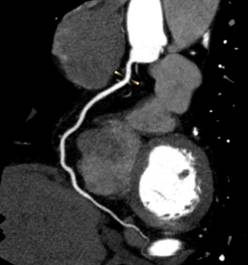

1、心脏检查时无需屏气,无需服药控制心率

Apex CT拥有160mm超宽体探测器,旋转一周仅需0.28s,即可以在一个心动周期内完成整个心脏的扫描。患者无需提早一小时来服药控制心率,高心率、房颤室颤、无法配合呼吸的患者都能在自然状态下接受检查,并通过高能量子球管使用的低kV高mA的扫描模式,在降低对比剂速率、用量和辐射剂量的同时,还能提高组织对比度,得到更高的密度分辨率,显示出更清晰的病灶。